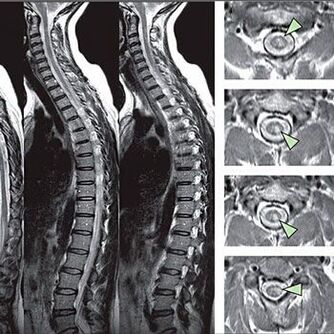

Métodos para diagnosticar osteocondrose da coluna torácica

Para um diagnóstico claro, o especialista deve levar em consideração as queixas do paciente. Os seguintes sintomas e sensações nas mulheres permitem detectar a osteocondrose mamária: quando pressionado em certos pontos na área do peito, uma síndrome da dor severa aparece.

Para identificar sinais de distúrbios de sensibilidade, são realizados testes funcionais especiais. A opção mais informativa do diagnóstico de métodos instrumentais é o desempenho de uma raio X. No entanto, para um estudo completo da coluna vertebral, a ressonância magnética e a TC são frequentemente realizados. Em caso de suspeita de doenças do sistema cardiovascular, o paciente é recomendado para passar pelo procedimento de ECG.